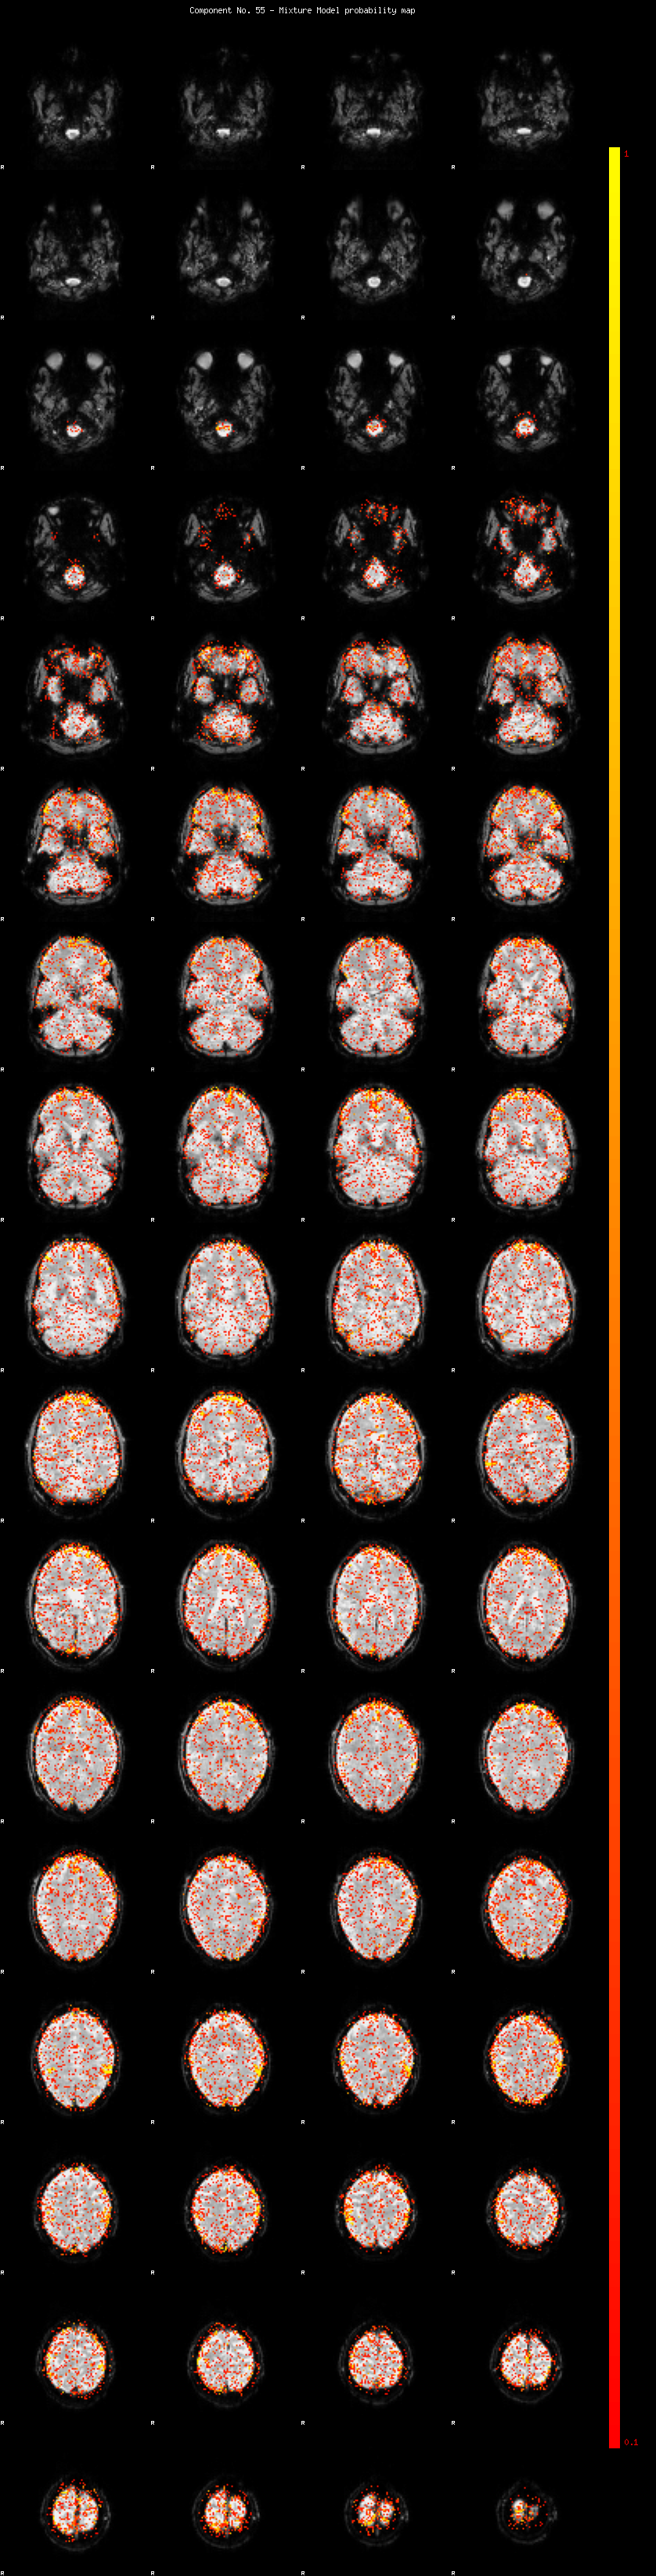

IC_55 Mixture Model fit

Means : -0.000000 2.266444 -2.231694

Vars : 1.000000 0.746183 1.208204

Prop. : 0.926658 0.021515 0.051826